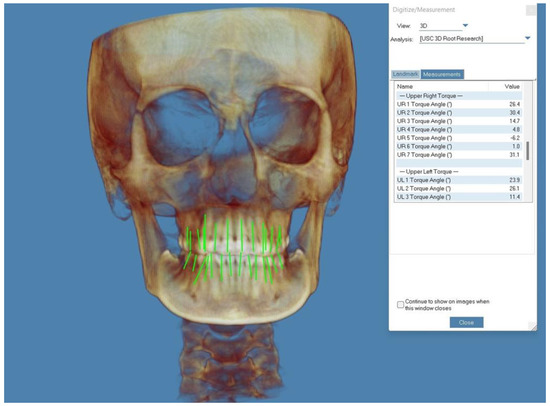

- Tong, H.; Enciso, R.; Van Elslande, D.; Major, P.W.; Sameshima, G.T. A new method to measure mesiodistal angulation and faciolingual inclination of each whole tooth with volumetric cone-beam computed tomography images. Am. J. Orthod. Dentofac. Orthop. 2012, 142, 133–143. [Google Scholar] [CrossRef] [PubMed]